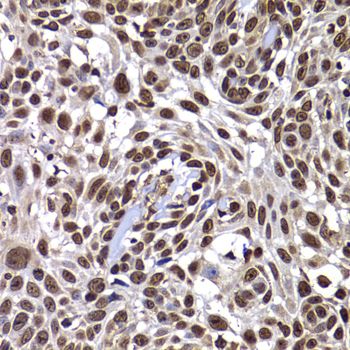

Immunohistochemistry of paraffin-embedded human well-differentiated squamous skin carcinoma using DNAJB6 antibody at dilution of 1:100 (x400 lens).